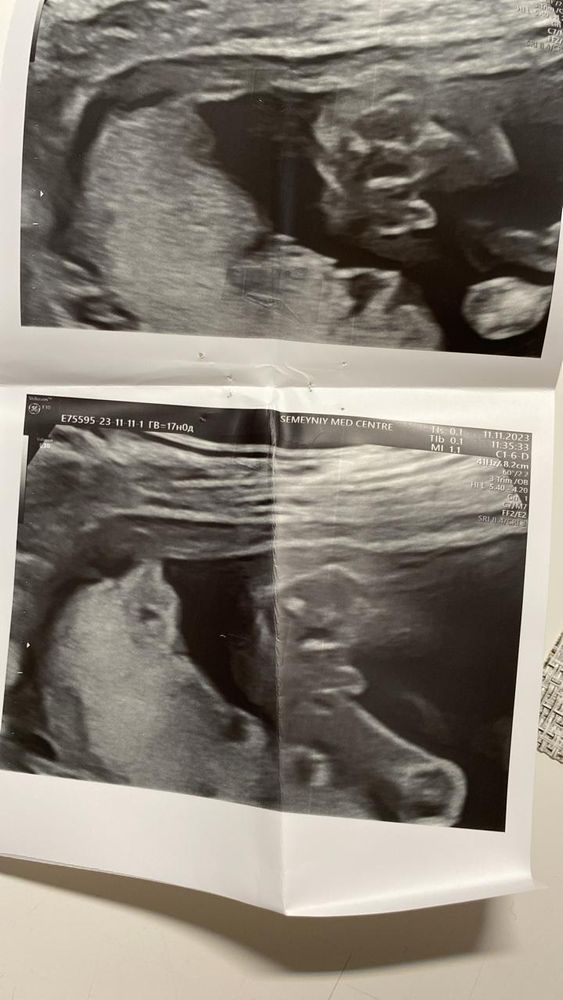

Узи мальчик

Пол малышаВсем доброго времени суток )

у нас было гендер - пати, и только после него открыли фото узи, у нас мальчик , но сколько бы я не разглядывала фото , не могу понять где увидели то самое мужское достоинство 🤭

Опытные, помогите понять🙏🏼